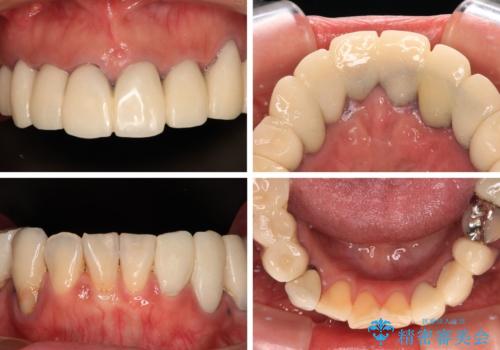

- 近医にて古いかぶせ物をセラミッククラウンにしようと治療を開始したものの、仮歯での咬み合わせが不安定とのことで、転院を希望して来院された患者様です。

骨格的に下顎骨が前方位に位置しており、上下前歯部の先端同士が接触する切端咬合でした。

このような方は咬み合わせが大きく変わると不安定となるため、まずは装着されている仮歯で咬合調整を行い、安定した咬み合わせとした後に、新しい仮歯に置き換え、その後オールセラミッククラウンにて補綴治療を行うこととしました。

仮歯で咬み合わせの調整を行ってからは、特に不安定になることもなく、非常にスムーズに治療を進めて行くことができました。

前歯奥歯ともに望ましくない力がかかりやすい咬み合わせであるため、就寝時にはマウスピースを使用するようにお伝えしております。